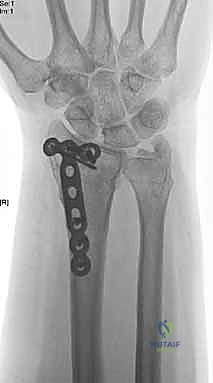

صورة طبية توضح كسر الناتئ الإبري

استخدام الأشعة السينية في التشخيص

1. الأشعة السينية (X-rays): بوضعيات متعددة (أمامية خلفية، وجانبية دقيقة). الوضعية الجانبية الحقيقية (True Lateral) حاسمة لاكتشاف أي خلع جزئي في المفصل (DRUJ).

صورة طبية: علاج كسور عظم الزند: دليل شامل لكسور الناتئ الإبري، الرأس، والجزء الكردوسي الكردوسي مع الأستاذ الدكتور محمد هطيف في صنعاء